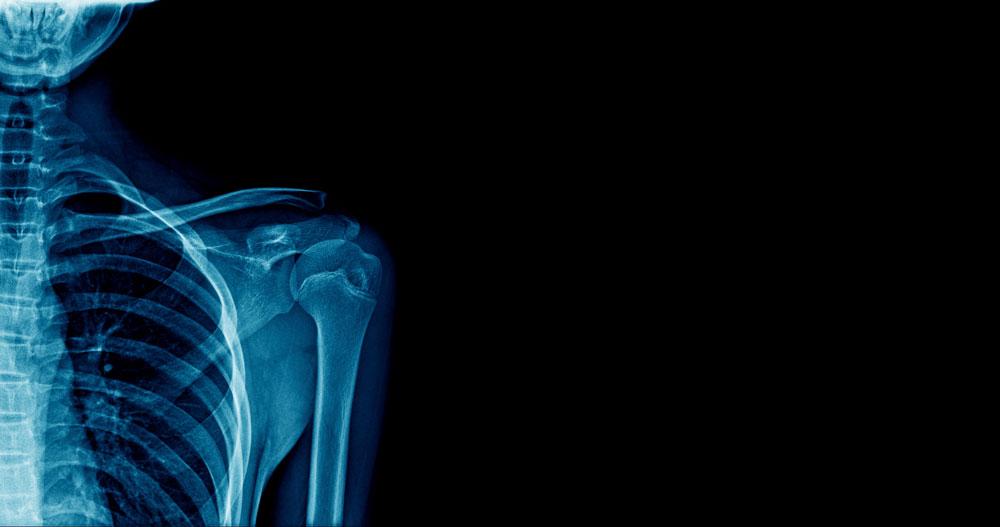

X-ray

The Royal Orthopaedic Hospital NHS Foundation Trust is running a clinical trial to investigate whether radiotherapy after surgery can significantly reduce pain in patients with secondary bone cancer.